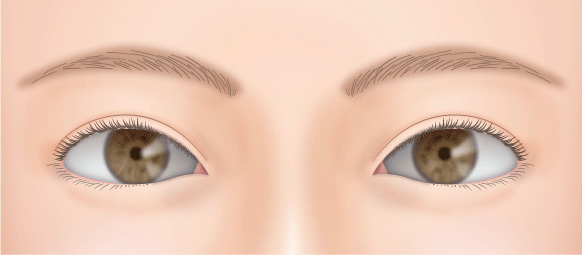

二重の幅が思ったより狭かった場合もあります。

切開法の場合、もう一度切開手術をすれば、可能な限り広げられます。

埋没法の場合は、あまり広くすると元に戻ってしまうことがあるので切開法での再施術をおすすめします。